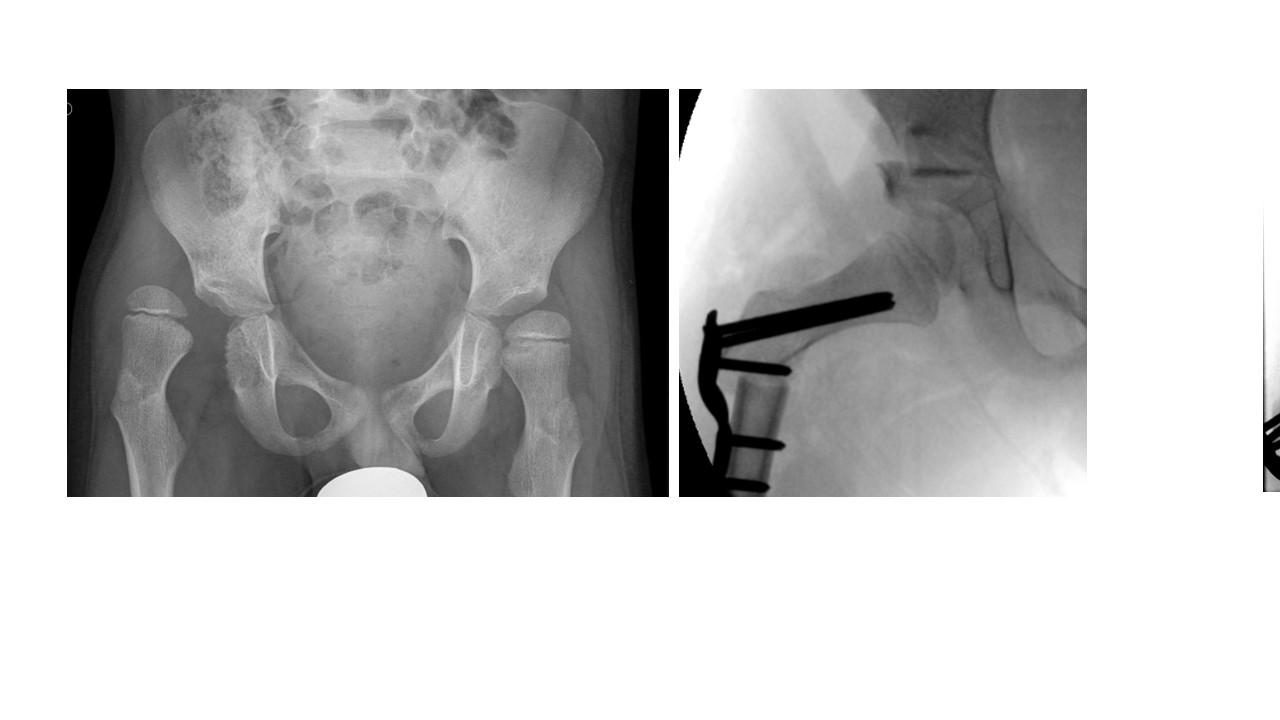

(a) zeigt einen 9-jährigen Patienten mit beidseitiger Minderüberdachung des Hüftkopfes und Steilstellung der Schenkelhälse. (b) zeigt den Zustand nach beidseitiger Beckenosteotomie nach Salter und Umstellungsosteotomie am proximalen Femur. Da der Eingriff in zwei Etappen erfolgte (zunächst auf der linken Patientenseite und dann rechts) sind rechts noch Salter-Stäbe einliegend. Zum Vergrößern auf das Bild klicken.